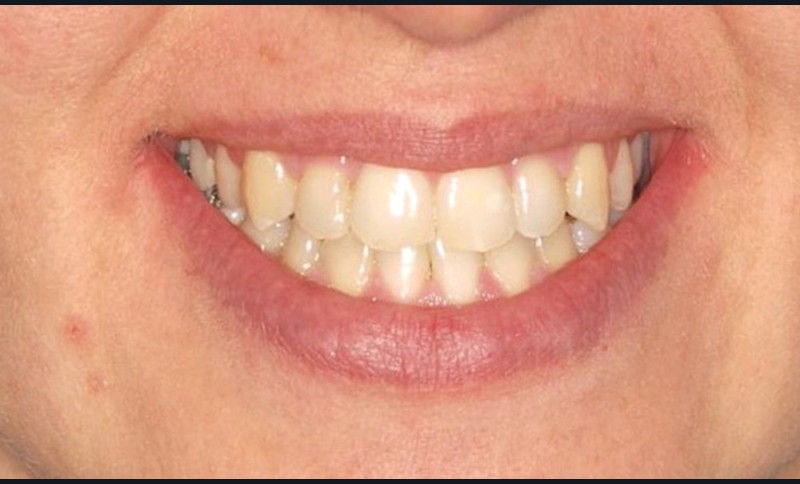

Diagnostic (fig. 1a-g)

La patiente présente une classe III squelettique dans un contexte hyperdivergent associée à une endoalvéolie maxillaire, un articulé inversé antérieur, une rétroversion incisive maxillaire, des rapports de classe I canine bilatérale, une absence de 16 et 36.

Au niveau esthétique, le profil est rectiligne. La lèvre supérieure est plus effacée, en retrait par rapport à la lèvre inférieure. De face et de profil, la mandibule paraît massive et le maxillaire effacé : le manque de soutien de la lèvre supérieure contribue à cette impression.

Le sourire est étroit, dégradé par les malpositions dentaires.

Au niveau fonctionnel, il existe un pro-glissement mandibulaire et un articulé inversé antérieur. Le profil téléradiographique montre en occlusion des rapports labiaux et un profil de classe III plus marqué que sur photographies.